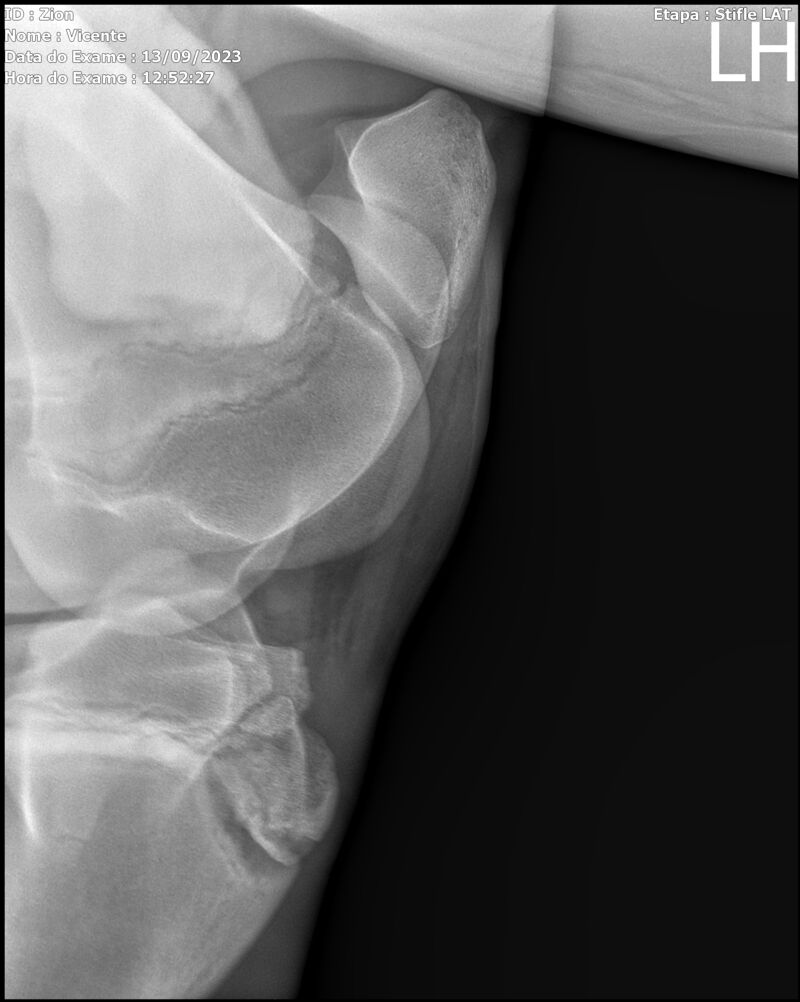

ZION ZC

Raça: BRASILEIRO DE HIPISMO

Sexo: MACHO - POTRO

Nascimento: 17/12/2022

Altura Aproximada: 1,51

Pel.: CASTANHO

Registro: EM AND

Vend.: VICENTE CONTE

Local : PORTO FELIZ/SP